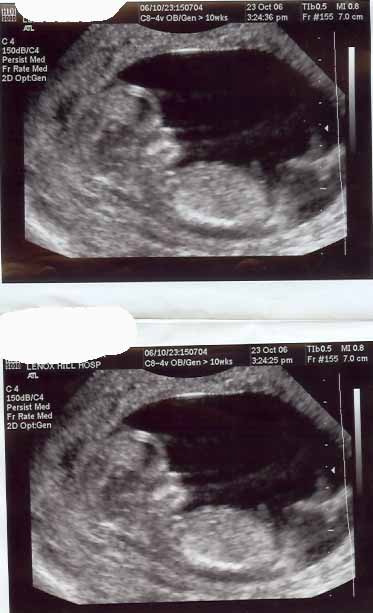

12 WEEKS... Image Attachment(s):